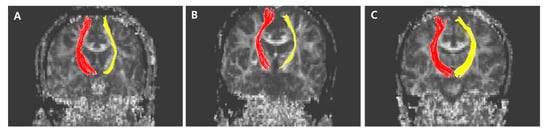

The normalized FA values of STT in the CPSP group were lower than those in the stroke control group and normal control groups; 0.79 for CPSP, 0.98 for non-CPSP, 0.98 for control (Figure 2A). The normalized FA values of STR in the CPSP group were lower than those in the stroke control group and normal control groups; 0.88 for CPSP, 1.00 for non-CPSP, 0.97 for control (Figure 2B). There were no differences in the FA values of STT and STR between the stroke control and normal control groups. The normalized FN values of STT and STR were lower in the CPSP and stroke control group than in the normal control group. However, there was no significant difference between the CPSP and stroke control for the normalized FN of STT and STR. Representative DTIs of STT in all three groups are shown in Figure 3, and those of STR in Figure 4.

Figure 4. Representative diffusion tensor tractography images of superior thalamic radiation in typical subjects from the (A) CPSP group, (B) stroke control, and (C) normal control groups. The non-affected tract is shown in red, and the affected tract in yellow.